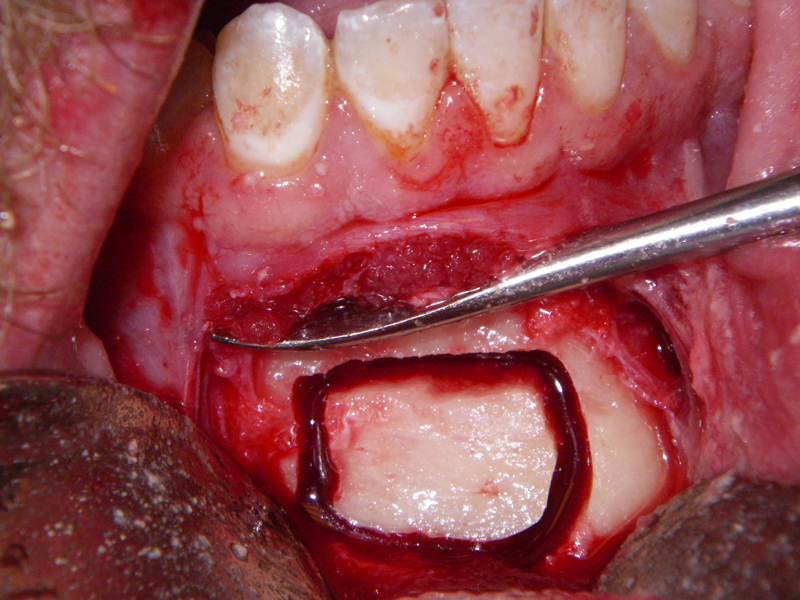

- Alveolar Ridge Augmentation

- Bone grafting – autogeneous, alogenic, xenogenic

- Blockgraft

- Socket presentation